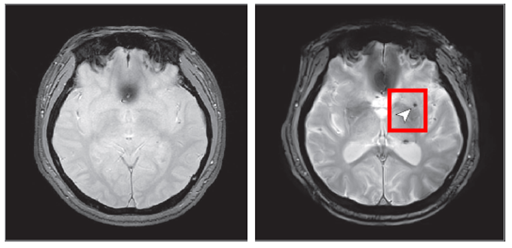

< 8년 후 뇌 미세출혈이 발생한 뇌영상 이미지 >

노화 기반 참여                     8년 후 추적조사 참여

뇌 미세출혈은 뇌 속의 작은 혈관이 손상되어 출혈이 발생하는 것으로, 뇌졸중(특히 뇌출혈) 등 심각한 뇌혈관 질환의 주요 위험요인으로 알려져 있다.

연구 결과, 중등도 이상의 폐쇄성 수면무호흡증을 가진 사람은 수면무호흡증이 없는 사람에 비해 뇌 미세출혈이 발생할 위험이 약 2배 증가하는 것으로 나타났다. 반면, 경증 수면무호흡증에서는 위험 증가가 관찰되지 않았다.